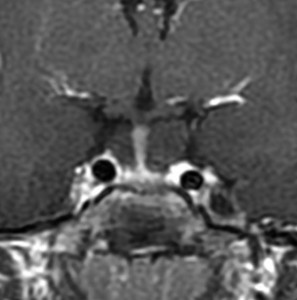

この画像はプロラクチンが上昇 (51ng/ml) して生理不順になった20代女性のものです。プロラクチン産生腫瘍には見えません。左の画像では嚢疱が2つ見られます。右の画像では,上の嚢疱に液面 fluid-fluid levelが見られて,腫瘍内の出血があったようにもみえます。手術後の病理診断は両方共にラトケのう胞でした。プロラクチン値は正常に戻りました。

でも手術中の所見では,上方のものは黄色肉芽腫のようで,のう胞内用液は頭蓋咽頭腫のように廃液用のドロッとした暗緑褐色のもので,さらにキラキラ光るコレステリンの結晶がたくさん出てきました。下の嚢疱は黄褐色の通常のラトケのう胞の内容液でした。両方ともに下垂体の正常腺組織とは区別がつかない繊維化した壁があって,危うく下垂体機能損傷を生じるところでしたが難を避けました。

このような腫瘍では下垂体機能障害を招いてしまうことが多いので,嚢疱を破るだけにとどめて壁となっている組織を積極的に摘出しない方がいいでしょう。下垂体腺腫でもなく頭蓋咽頭腫でもなく,炎症性組織あるいは肉芽腫様に見えたら切除を中断することが肝要です。